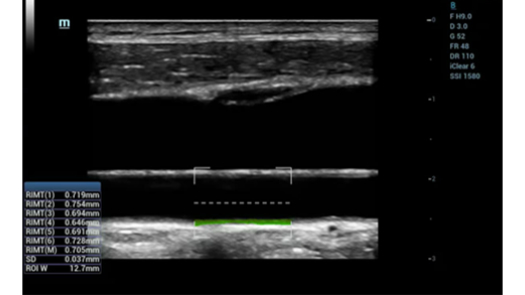

??? ??

? ???? ??? ???? ??

? ??? ???? ?? ???? ?? ??